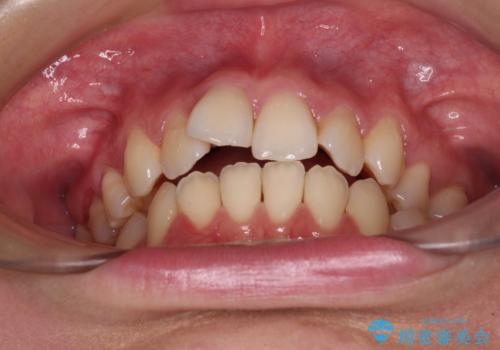

- 抜歯矯正の後戻りを気にして来院された患者様です。

舌の突出癖によるオープンバイトになっていたため、インビザラインによるマウスピース矯正をおすすめしましたが、自己管理の自信がないとのことで、ワイヤー装置による矯正治療を行うこととしました。

舌の突出癖が認められると、上下前歯の隙間を閉じることができません。

舌のトレーニングをしっかりと行っていただくことで、歯列を整えることができます。